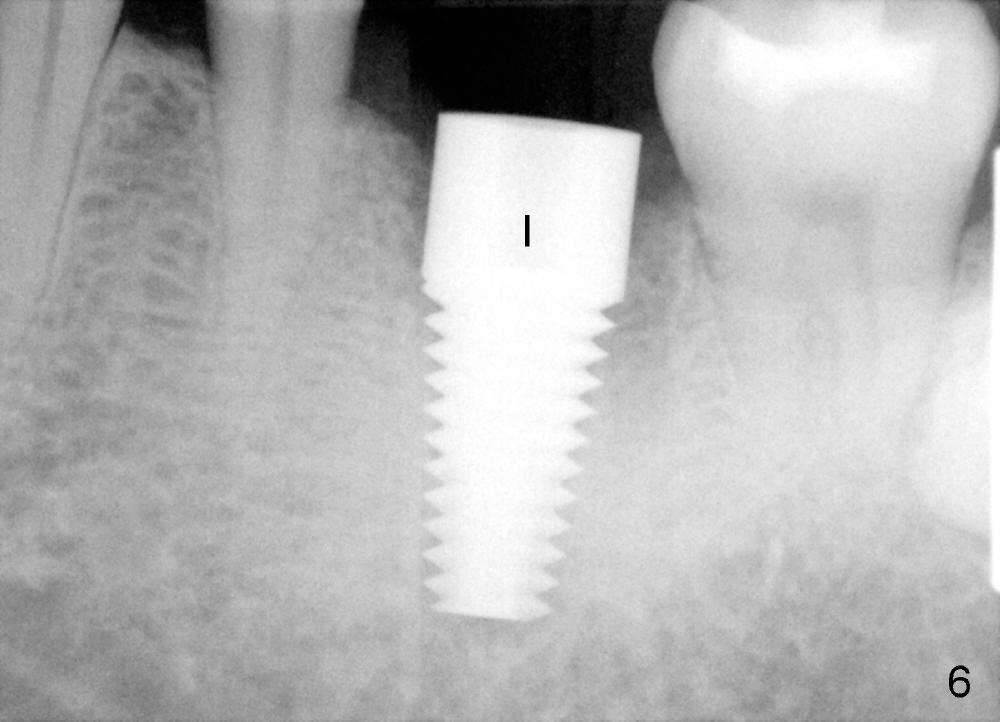

A 41-year-old man has discomfort in the lower left 1st molar. Exam shows swelling and a fistula in the mesiobuccal gingiva (Fig.1 >) and large radiolucency around the mesial root (Fig.2 *). After extraction and thorough debridement, osteotomy is initiated in the mesial socket, but the upper portion of the reamer (Fig.3 R, 2.5 mm) is placed in the middle of the edentulous space. By the time 5 mm reamer is removed, the osteotomy (Fig.4 O) forms mainly in the mesial socket with the septum (S) deviated to the distal socket. A 7x17 mm tap is placed with stability (Fig.5 T). An implant with the same dimension is placed with insertion torque more than 60 Ncm (Fig.6 I). With the large implant, two proximal sutures are able to close the remaining socket gaps (Fig.7). The swelling and fistula disappears and the gingiva tightly surrounds the implant in 1 week postop (Fig.8).

There is a thick gingival band buccal to the implant 7 months postop (Fig.9 *). Osteointegration occurs (Fig.10). The most unexpected finding is the formation of the papillae (Fig.11 *) when the permanent crown is seated. The cosmetic result is due to immediate placement of the large implant. Delayed implant usually cannot achieve this type of outcome.